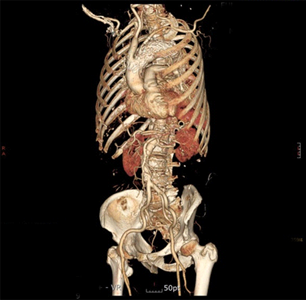

하이브리드 대동맥 수술

술전 CT (대동맥궁 대동맥류) 대동맥내 스텐트 삽입 및 머리혈관 우회술

술전 CT

머리혈관 우회술

술 후 가슴사진 및 술 후 CT

술 후 가슴사진

술 후 CT